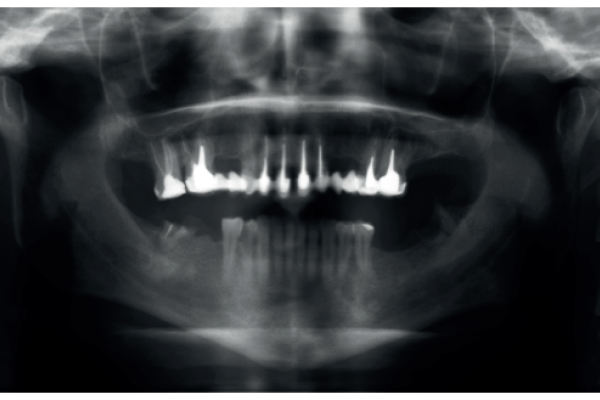

3 | CASO CLÍNICO | ENFOQUE CONSERVADOR EN PACIENTE CON MÚLTIPLES LESIONES PERIAPICALES RADIOLÚCIDAS: ABORDAJE COMBINADO ENDODÓNTICO-QUIRÚRGICO |